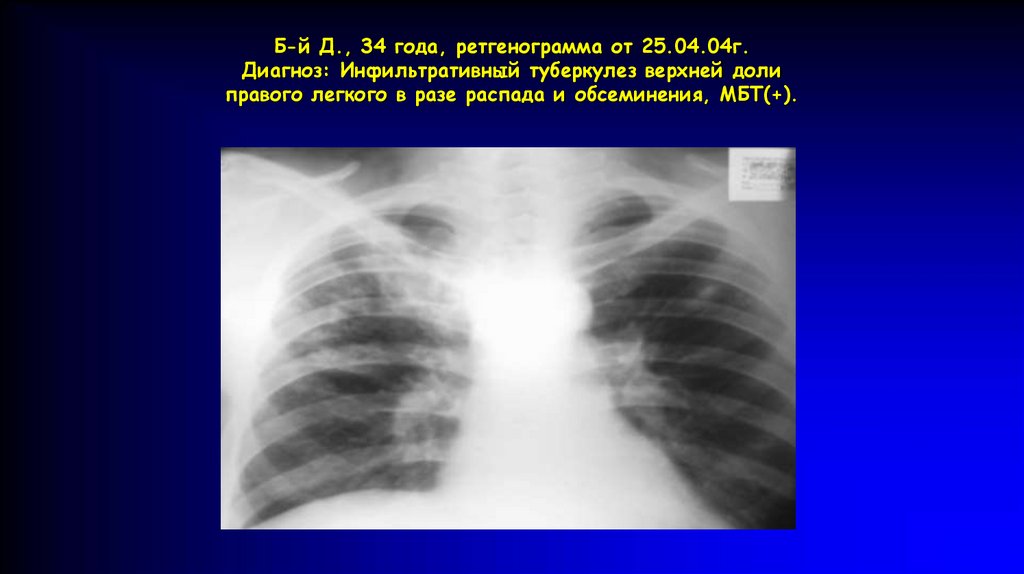

Б-й Д., 34 года, ретгенограмма от 25.04.04г.

Диагноз: Инфильтративный туберкулез верхней доли

правого легкого в разе распада и обсеминения, МБТ(+).